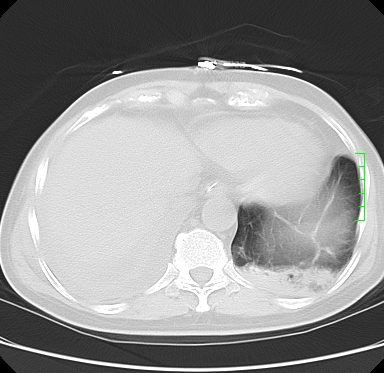

icu病人,几天都没明确诊断。m,76y,咳嗽、咳痰1周,伴气促,右胸痛入院,pe:t38.3c p135 r25 bp135/85。双肺可闻及大量湿罗音,心、腹未见明显异常。诊断:1心衰?2肺部感染?3冠心病?

11号ct

大叶性肺炎、胸腔积液

双肺感染性病变,下叶膨胀不全,胸水,左室大。

1)两肺感染性病变(右肺下叶肺脓肿可能)。2)双侧胸腔积液,以右侧为甚。

考虑双肺感染、右肺下叶肺脓肿伴双侧胸腔积液。

ards,肺感染性病变,右下叶实变,双侧胸腔积液,右侧为著,叶间胸膜积液,右上肺陈旧性tb纤维灶,左室大。

考虑双肺感染、右肺下叶肺脓肿伴双侧胸腔积液,肺水肿。

考虑:双肺感染、右肺下叶肺脓肿,双侧胸腔积液,肺水肿.请结合临床.